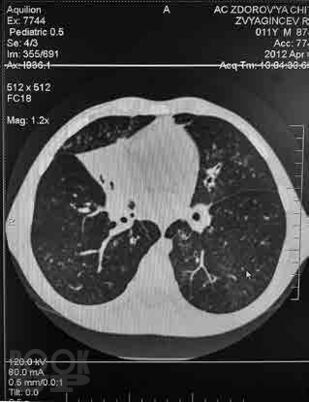

Сборник включает вызвавшие наибольший интерес аудитории лекции и доклады на различных научно-практических конференциях в 2018–2019 гг. по актуальным проблемам пульмонологии и аллергологии детского возраста, таким как: современные методы диагностики и лечения, острые и хронические инфекционно-воспалительные и аллергические заболевания органов дыхания, муковисцидоз, туберкулез органов дыхания, а также обмен опытом, интересные случаи из медицинской практики, различные другие информационные материалы. Ежегодник адресован практикующим детским пульмонологам и аллергологам.